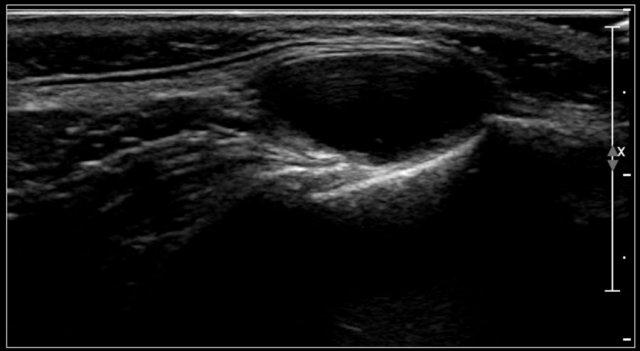

Video cho thấy một khối sưng xuất hiện qua đêm ở một bé gái 13 tuổi.

Một tổn thương giảm âm được nhìn thấy nằm nông so với động mạch cảnh và sâu so với cơ ức đòn chũm.

Không thấy sự di chuyển của nội dung tổn thương khi gõ nhẹ bằng đầu dò.

Khi bé gái được yêu cầu ngồi thẳng, nội dung bên trong xoáy chuyển động.